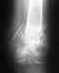

Можно порекомендовать по крайней мере до заживления раны фиксацию аппаратом. После заживления мягких тканей решать о целесообразности смены наружной фиксации на блокируемый стержень. Для более определенных ответов не хватает информации о том, что именно с раной сейчас. Где сейчас больная? Это насчет "куда можно обратиться".